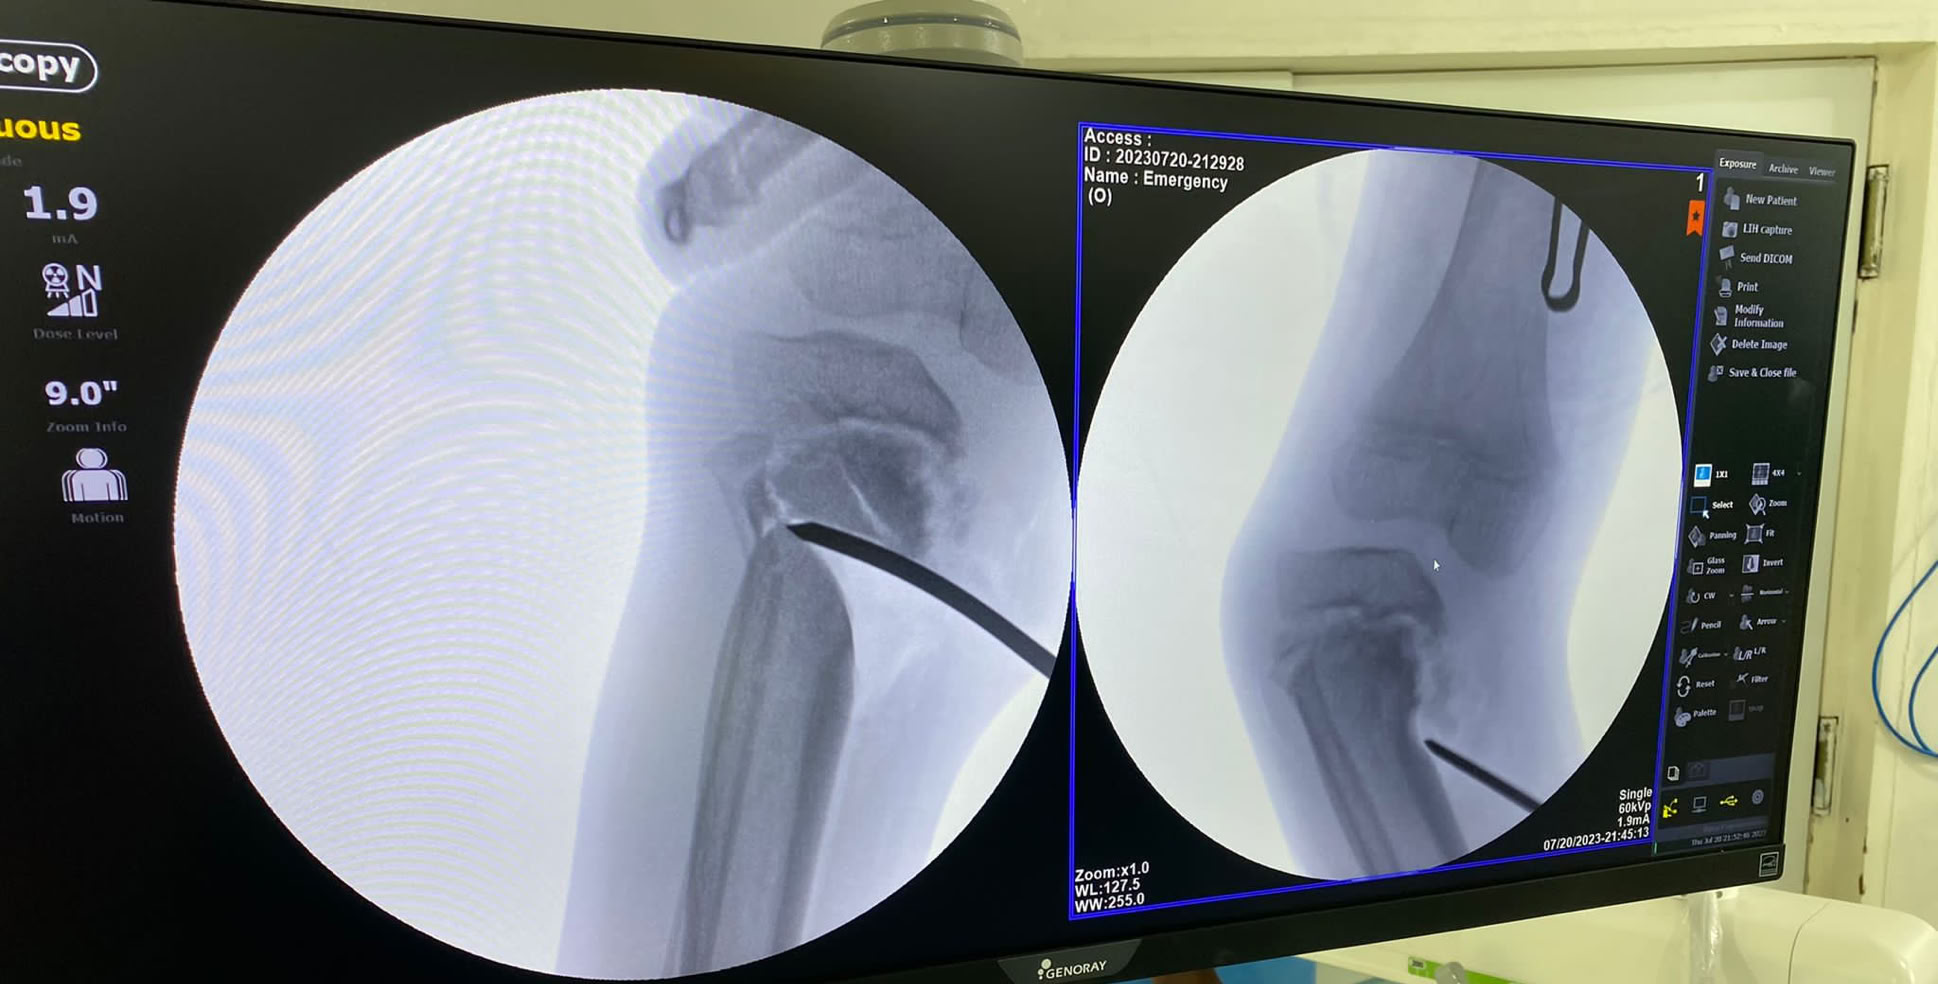

Las sesiones quirúrgicas se han podido dividir entre todos los integrantes pudiendo llevar a cabo a dos quirófanos varias cirugías entre ellas un caso complejo de fractura luxación de cadera con tibia bifocal homolateral consecuencia de los tan frecuentes y graves accidentes de moto.

En la consulta se fue fraguando lo que iba a ser nuestro quirófano a lo largo de la estancia pudiendo comprobar que la situación endémica de fracturas de tibia en todas sus modalidades continua sin cambiar. En total se han realizado 23 cirugías entre las que cabe destacar el caso anterior, ademas de 5 seudoartrosis de tibia, dos fracturas de fémur, una fractura luxación Lisfranc, de radio, seudoartrosis de humero y varios casos de cirugía de mano y miembro superior pues nos acompañaba el Dr. Galan . Ademas se han realizado varias limpiezas quirúrgicas de osteomielitis, osteítis y movilización séptica de una PTC, injertos de piel y un solo caso de ortopedia infantil de un Blount, realizado por el Dr. Nges. Poco a poco la autonomía para la resolución de los casos es mayor por parte del equipo local sin dejar de introducir nuevas técnicas como el enclavado humeral.